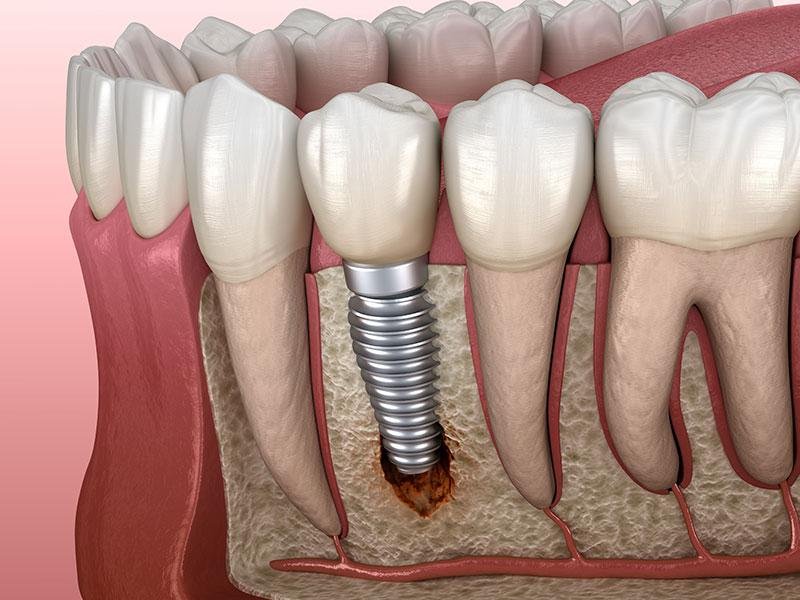

یکی از بزرگترین ریسک ها، پدیده ای به نام پری ایمپلنتایتیس یا التهاب اطراف ایمپلنت است. در این وضعیت، بافت های اطراف ایمپلنت دچار التهاب و تخریب استخوان می شوند. سیگار با کاهش جریان خون در این ناحیه باعث می شود که سیستم ایمنی دهان نتواند باکتری های مضر را به خوبی از بین ببرد و در نتیجه، التهاب تشدید گردد.

ریسک دیگر، شکست جوش خوردن ایمپلنت با استخوان یا همان Osseointegration failure است. نیکوتین و سایر مواد سمی موجود در دود سیگار مانع رشد سلول های استخوانی جدید می شوند. در بسیاری از افراد، پس از چند ماه، ایمپلنت لق می شود و نیاز به خارج کردن دارد. همچنین، احتمال سیاه شدن یا نکروز بافت های اطراف ایمپلنت نیز در افراد سیگاری بالاتر است. این وضعیت گاهی منجر به درد، ترشح، بوی بد دهان و از دست رفتن کامل ایمپلنت می شود.